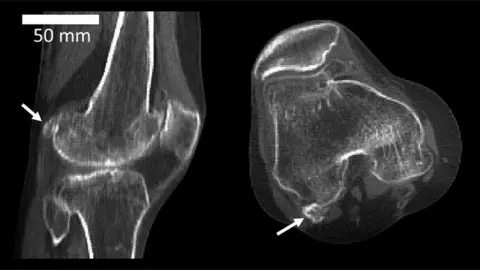

Imperial College LondonA little bone in the knee scientists thought was being lost to evolution seems to be making a comeback, say experts from Imperial College London.

Imperial College LondonWhy do some of us have it?